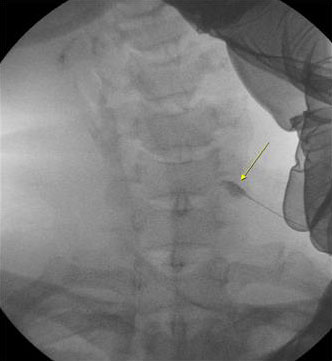

위에 노란색 화살표시부위가 조영제로 염색된 경추 7번 신경근입니다.

사진과 같이 조영제를 이용하여 정확하에 신경근의 위치를 파악한후 약물 (국소마취제 + 소량의 스테로이드 + 유착방지제)을 투여합니다.